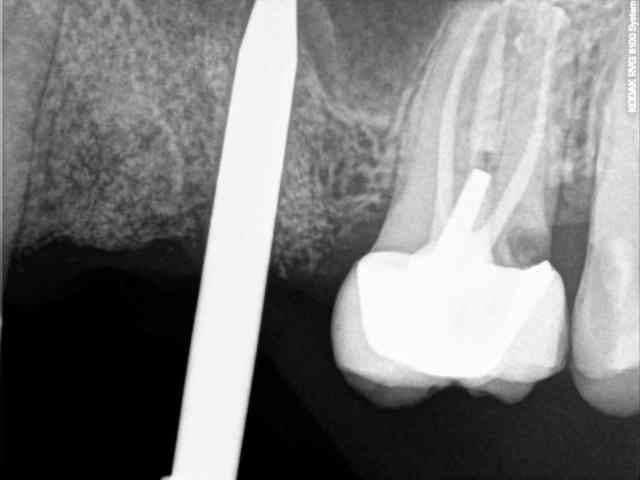

7-8-9-10-11- les radios

ici, tu l'as compris, ce n'est pas vraiment nécessaire excepté pour la 2 ième prémolaire où l'extraction est très récente (2 mois à peine) et où l'alvéole à été comblée par un biomatériaux.

gaffe quand même sous la couronne en distal.

Ah oui, gaffe avec la 26, gros bobo en distal.

la 26 oui, j'ai vu . mais aussi la 27 en mésiale...